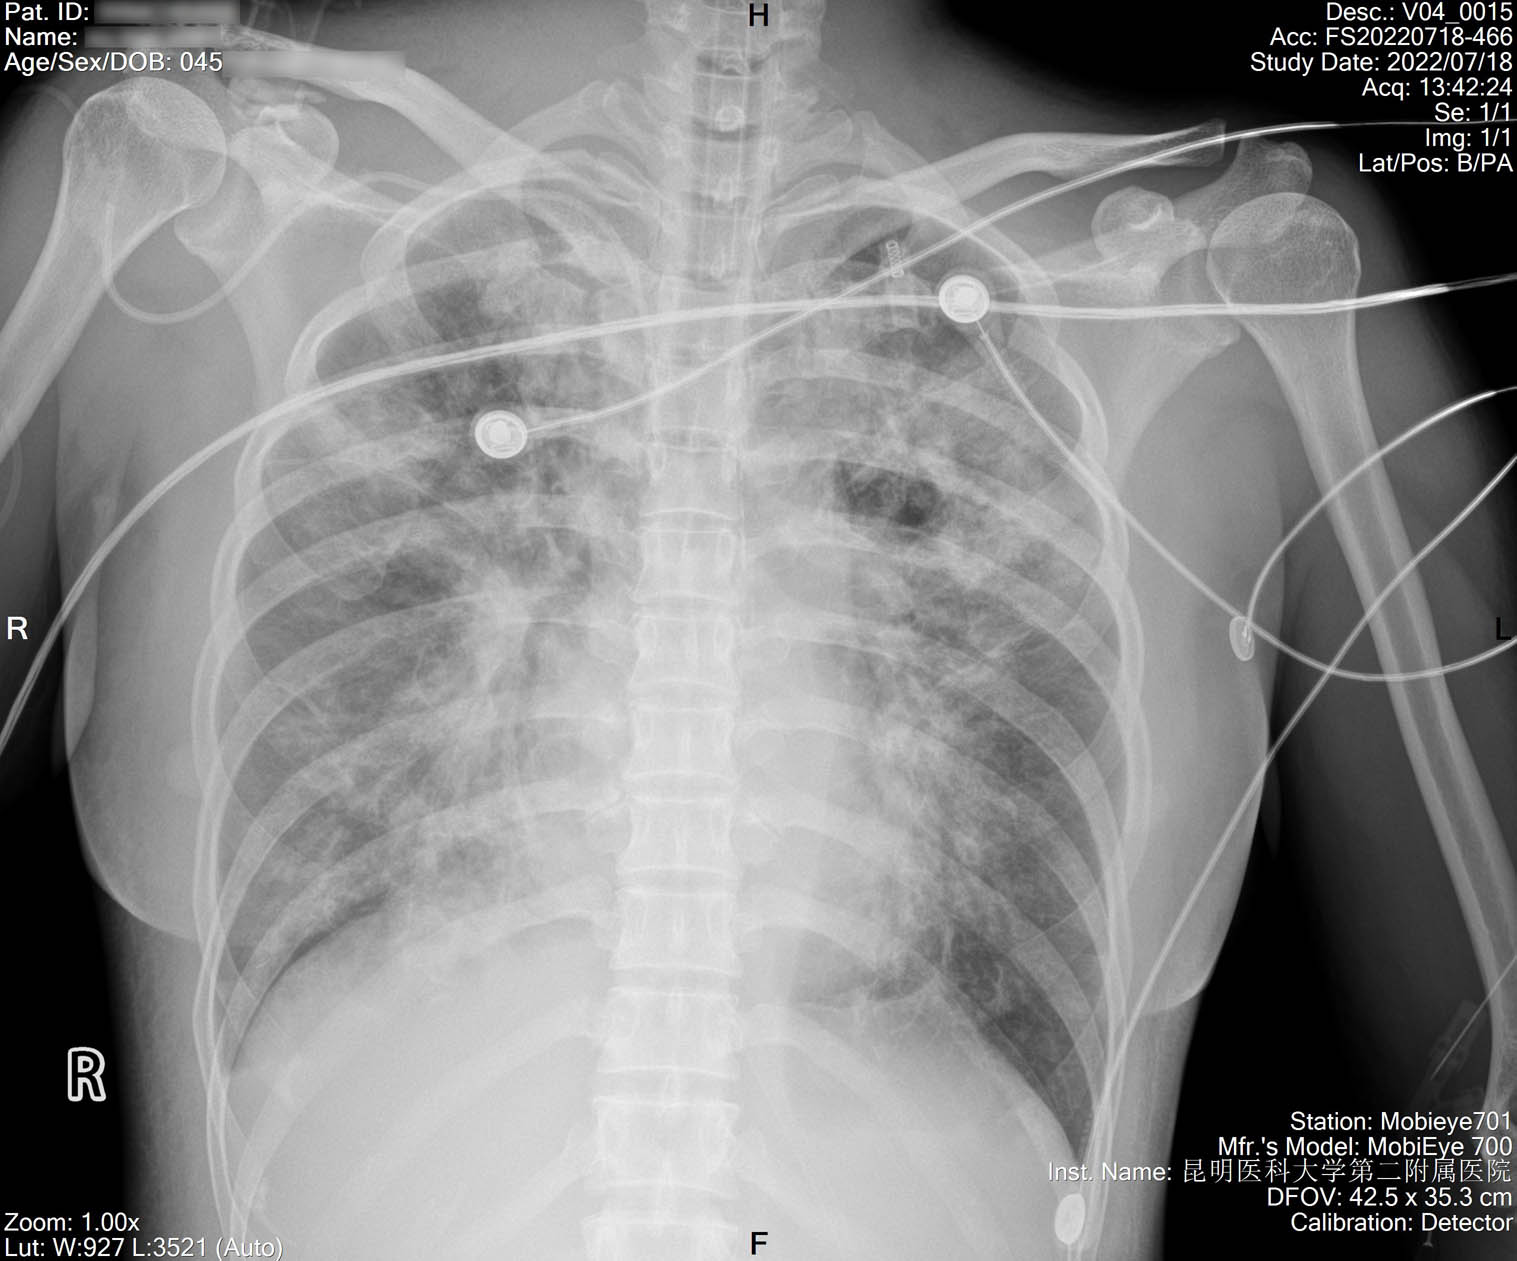

2022-07-16_胸片